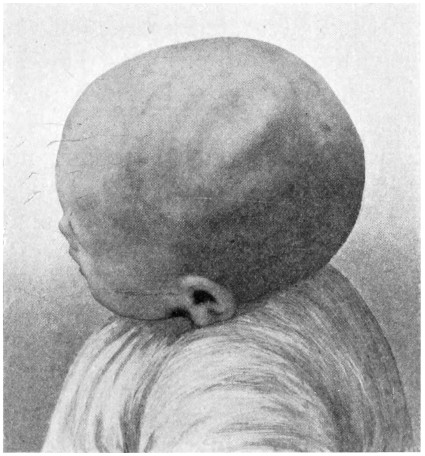

| 22. An occipital cephalocele | 37 |

Sincipital cephaloceles are usually quite small, but the occipital variety and those situated in[35] the region of the anterior fontanelle frequently attain a great size (see Figs. 20-22).

Fig. 22. An Occipital Cephalocele. (For further description, see text.)

The child was 3 months old, and presented a tumour, the size of an orange, situated between the occipital protuberance and the nape of the neck. The mass was pedunculated, the stalk being about the size of a four-shilling piece in diameter. It was soft, translucent, irreducible, and swelled up on coughing. An attempt at removal was carried out, and, after incising the outermost layers, three ounces of cerebro-spinal fluid escaped. A second tumour was then found occupying the base of the swelling. This was also punctured, more fluid escaping. Both sacs were cut away and the wound sewn up. Death occurred on the third day, preceded by convulsions, retraction of the head and neck, and high fever. The autopsy showed that the fontanelles were widely open, the anterior measuring 4 inches from side to side and 21⁄2 from before backwards. The bones of the vault were markedly thinned. In the subdural space there was a quantity of fluid, and the cerebral substance was soft and diffluent, the convolutions flattened, and the ventricles distended. There was a broad gap in the occipital bone, extending downwards into the foramen magnum, and in this situation the cerebellum had bulged backwards into the protruding mass. (See Fig. 22).